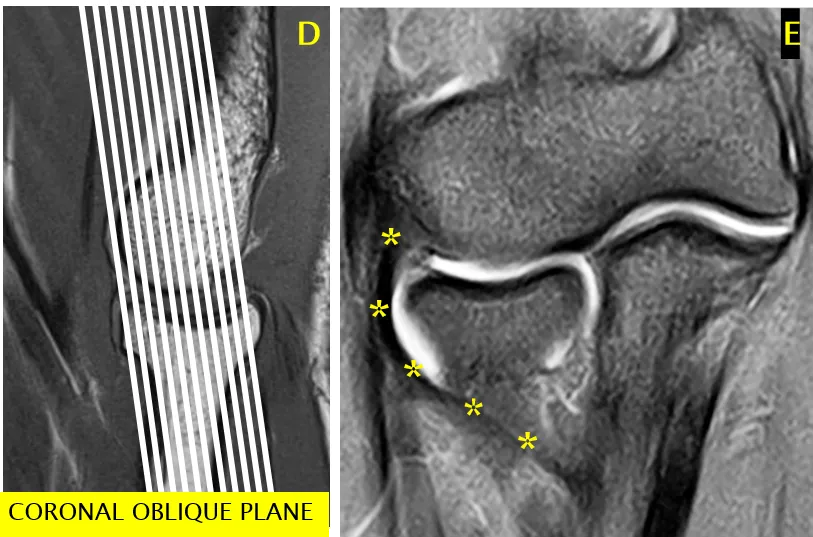

外侧尺侧副韧带(LUCL)最佳显示方式

• 肘关节伸直时,采用相对于肱骨干呈 20° 后斜的冠状面(图中白线标注)

• 肘关节屈曲 20°-30° 时,采用与肱骨干对齐的冠状面

• 配图:标注 D 的示意图,展示后斜冠状面位置

外侧尺侧副韧带显示示意图标注 D、E(E 中标注 LUCL 位置)